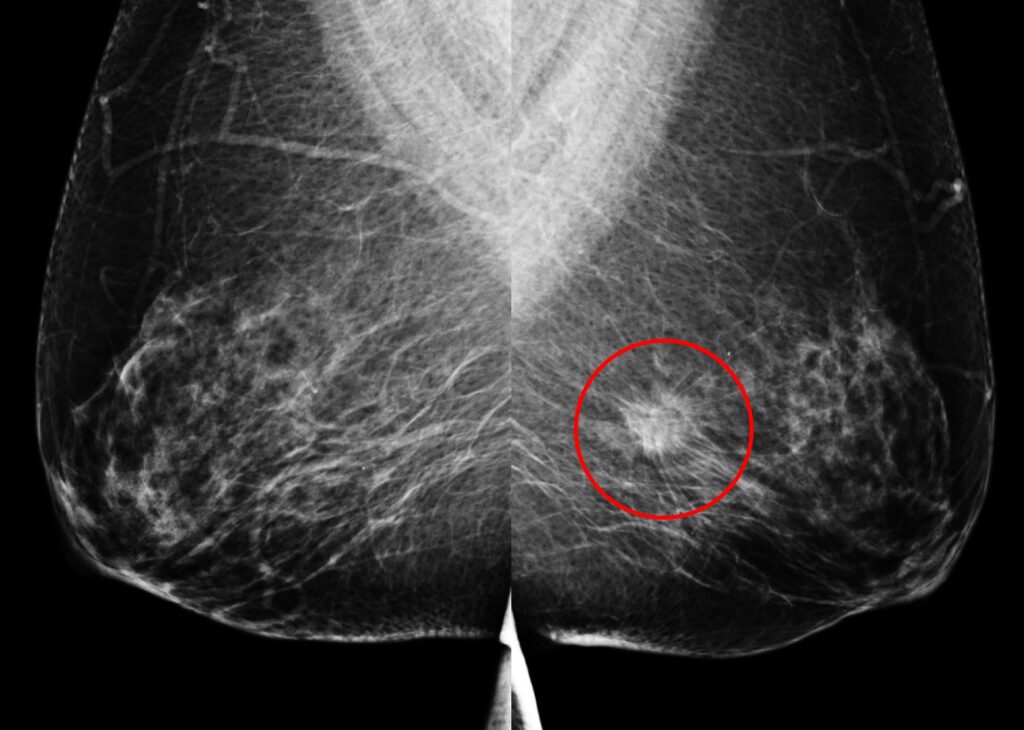

乳房X光攝影

另一名55歲女性於國健署「乳房攝影篩檢」發現:左乳下方有一局部腫塊合併組織變形,經切片證實為早期乳房侵襲癌。